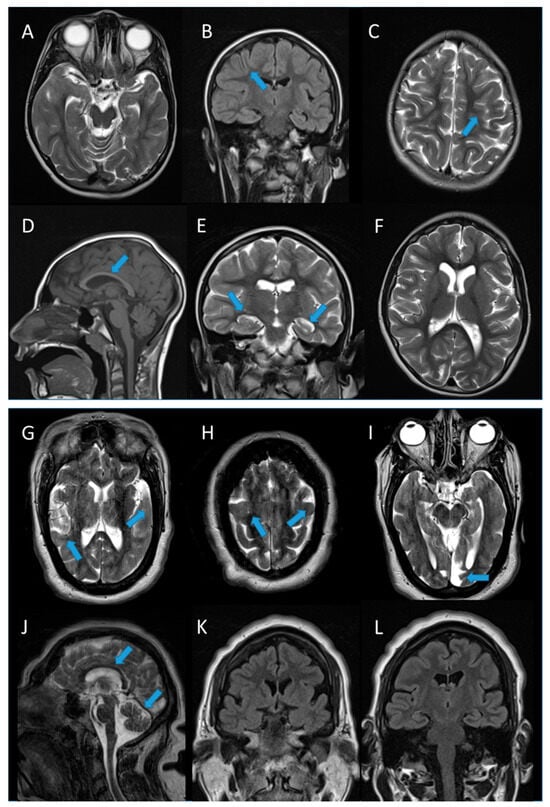

| 1 | c.148C>G (mother); c.742C>T (father) | p.Gln50Glu; p.Gln248Ter | missense; nonsense | compound heterozygosity | ƒ = 0.00000796 (rs756746191) ƒ = Not found (novel) | Pathogenic (PM3; PM2; PP5; PP2); Pathogenic (PM3; PM2; PVS1) | Male | growth deficiency, pyramidal signs, clumsiness, apraxic gait | large ear pads, arched eyebrows, flat nasal saddle, short philtrum, thin upper lip, microretrognathy, large incisors | yes | severe | 6 years | focal | poor organization | multifocal | microcephaly, simplification of cortical convexities, thin corpus callosum, dysmorphic hippocampi, enlarged and dysmorphic lateral ventricles | VPA, LEV | CBZ, CLB, LCM |

| 2 | c.1253_1269dup (mother); c.1386+49_1387-33del (father) | p.Thr424GlyfsTer49; exon 15 skipping | nonsense; nonsense | compound heterozygosity | ƒ = 0.000169 (rs587784365) ƒ = 0.0000699 (rs752902474) | Pathogenic (PM3; PM2; PVS1; PP5; PP3); Pathogenic (PM3; PM2; PP5) | Female | reduced weight growth, delayed psycho-motor development | receding forehead, hypertelorism, epicanthus, enlarged nasal root, wide mouth, micrognathia | yes | severe | 13 months | focal | diffuse slowing | right occipital focal activity | microcephaly, simplified cortical gyration, a previous left occipital vascular lesion, thin corpus callosum, small cerebellar vermis, moderate enlargement of lateral ventricles, diffuse thickening of the bilateral skull vault | PB, CBZ, GVG | VPA, CLB |